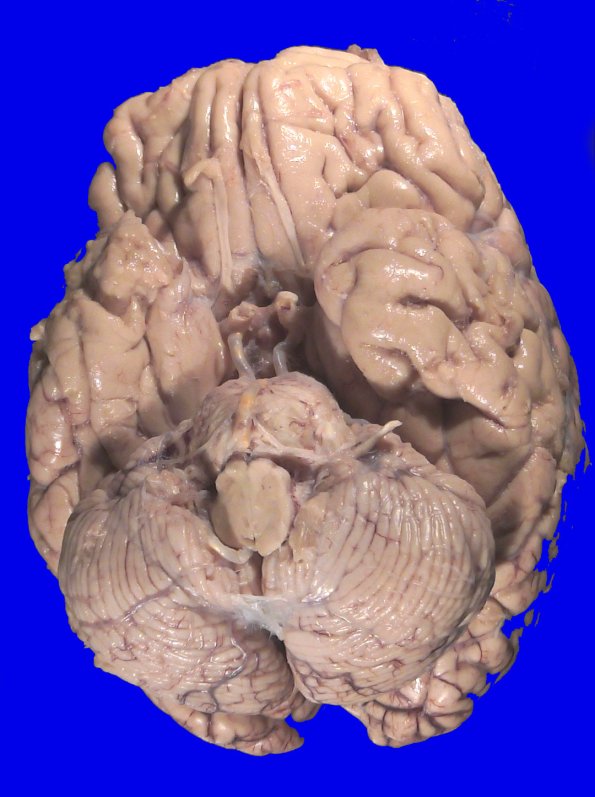

Washington University Experience | NEOPLASMS (HEMATOLYMPHOID) | Lymphoma, secondary | 14B1 Lymphoma, Pons (Case 14) Gross_1

At autopsy the weight of the unfixed brain was 1280g. The external surface of the brainstem and cerebellum are unremarkable and the leptomeninges are thin and translucent.